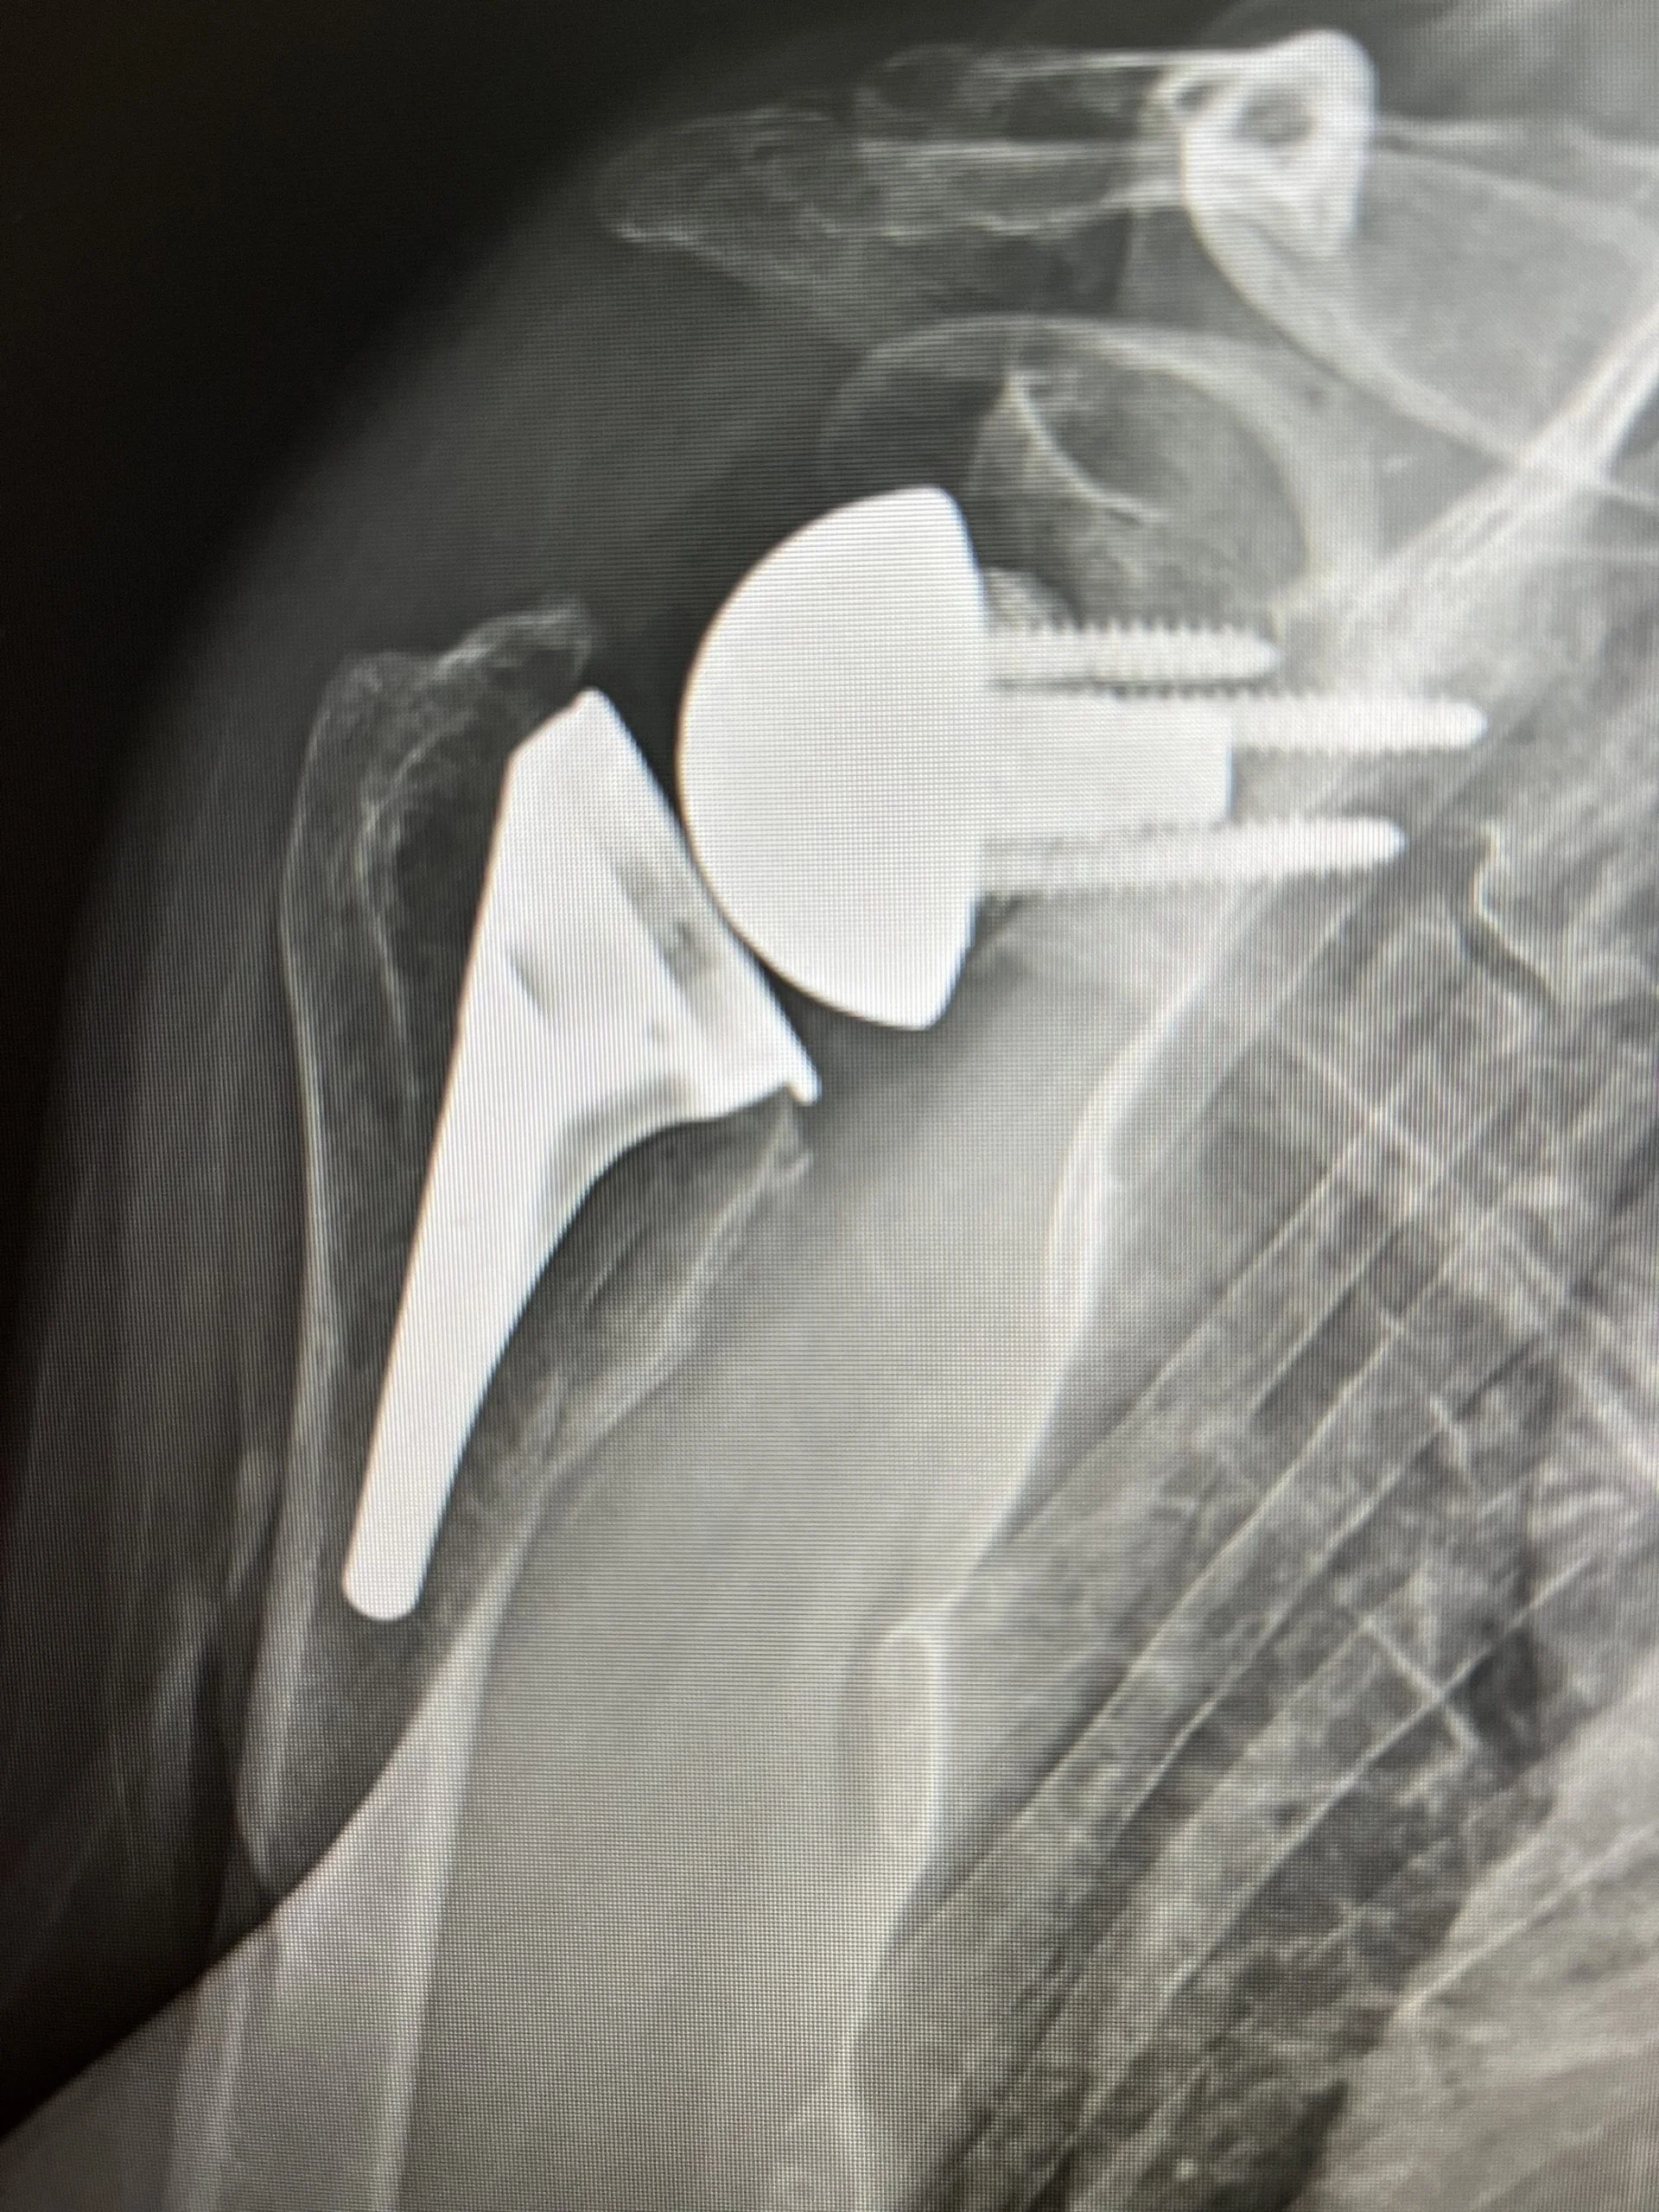

4. After preparing the arthritic surfaces, a new ball and socket are placed in the reverse orientation.

Reverse Total Shoulder replacement (shoulder arthroplasty) surgery overview

Total shoulder replacement surgery consists of 6 simple, but yet complex steps: